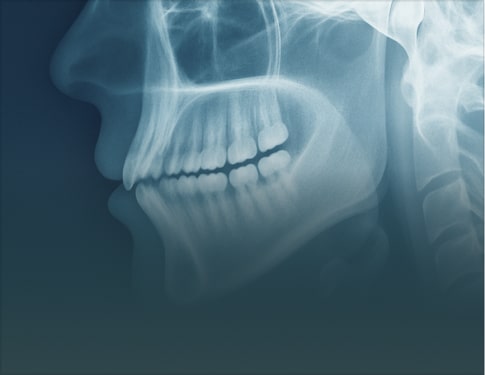

Advanced Report includes annotated images, detailed key findings, and practical clinical recommendations. Choose this option for treatment planning, complex cases, referrals, or when visuals are needed to communicate findings with colleagues or patients and support confident clinical decisions in the final report.